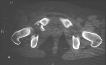

Radiographs:

Radiographs revealed a vertical buckle fracture of the right inferior sacrum, oblique fractures of the superior and inferior rami on the right and a fracture through the medial acetabulum. Obturator and iliac oblique inlet and outlet pelvic views, and a thin cut CT with 3-D reconstruction of the acetabulum were performed. These elucidated a comminuted anterior wall with fracture line extending to the posterior column. The posterior column was non-displaced. The pelvic fracture was non-displaced.

COMPUTED TOMOGRAPHY: R/O intra-articular loose fragments, Plan for surgery.